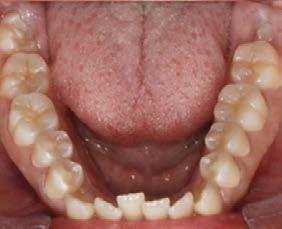

Caso clínico: paciente femenino de 19 años, patrón dolicofacial, perfil convexo, clase II esqueletal debido a una retrusión mandibular, mordida abierta anterior esqueletal, clase II molar, clase canina no establecida por mordida abierta, apiñamiento severo superior e inferior y deglución atípica.

Resultados: obtención de una clase canina I y clase molar II funcional, se corrigieron las sobremordidas horizontal y vertical, y se logró la coincidencia de líneas medias facial y dental. El manejo de la mordida abierta anterior se llevó a cabo por medio de la corrección del hábito de deglución atípica con la ayuda de spikes de resina, elásticos intermaxilares y arcos utility, y se obtuvieron buenos resultados estéticos, dentales y funcionales.